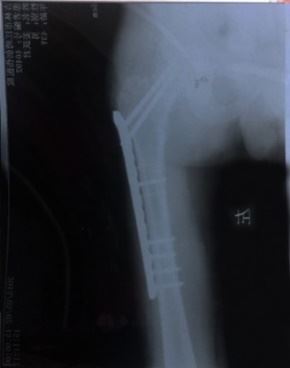

一直由姜跃军赡养的岳母患有肝病,因担心女婿而吐血病危住院。姜恳请“610”人员让他回家探望岳母,可他们完全不计人伦,不顾亲情与孝道地说:死了也不准!别说是岳母呀,就是亲妈死了也许能有一点点可能!万般无奈之下,姜跃军于9月20日从洗脑班二楼跳下,导致大腿骨粉碎性骨折。妻子得知消息去医院护理丈夫,结果遭国保大队张学涛、南城派出所曹凤坤、夏春林等大量警察绑架并拘留(拘留结束后又直接转到吉林市与舒兰市两处洗脑班继续迫害)。

一天之内女婿腿断,女儿被抓,警察抄家,七八个警察将家里翻得一片狼藉,二老二小无人照顾,这沉痛的打击使病情刚有好转的岳母无法承受,身体不支,吐血住院,并在10月25日含冤离世。老人临终前还牵挂着女婿,说要去看他,可到最后都没能见上女婿一面,使在场的人无不动容流泪……

短短两个月的时间,洗脑班的迫害就致使这个幸福的家庭一亡一伤。

'姜跃军腿部术后照片'

姜跃军腿部术后照片